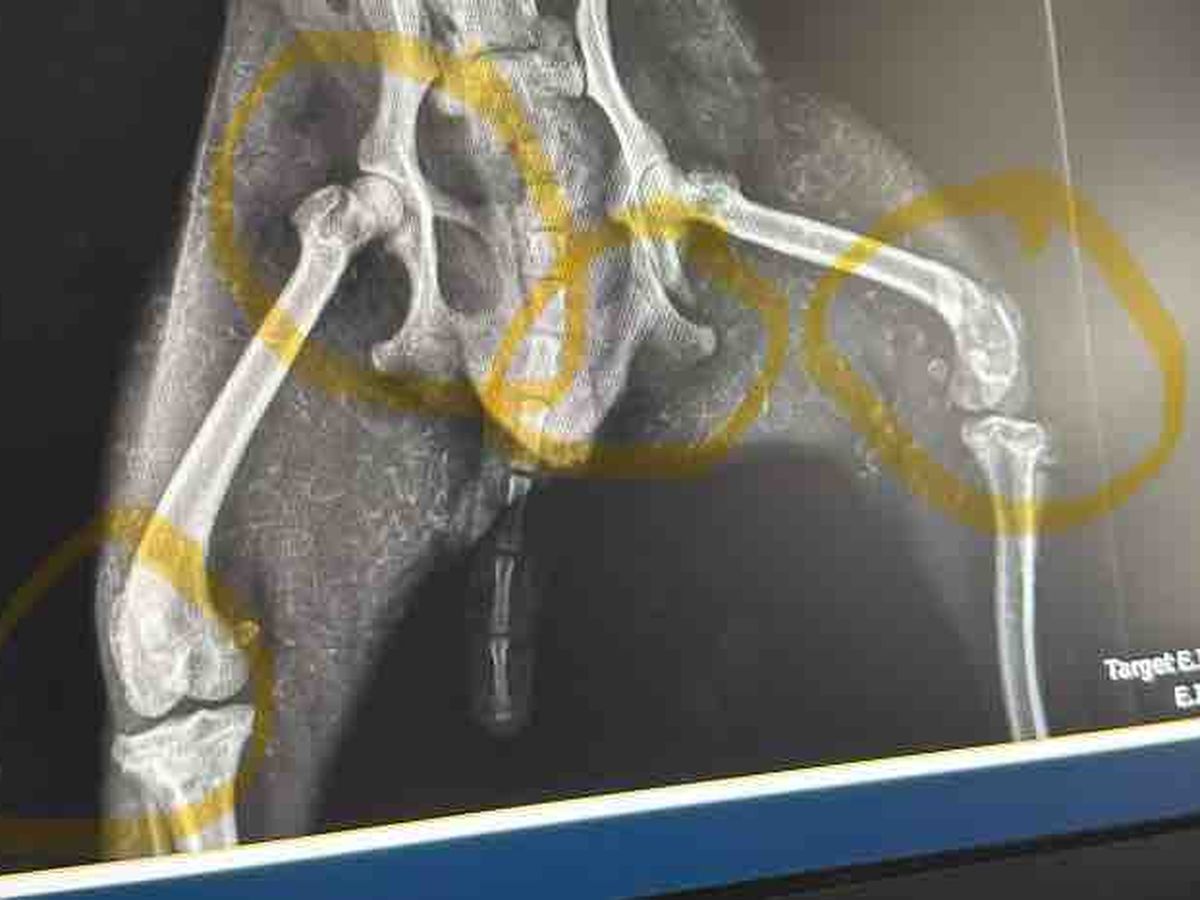

Bobo has back legs broken and a pelvic break, and will need a lot of surgery to be able to walk normally again. Anything helps